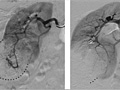

An angiogram is an X-ray test that uses dye and imaging (fluoroscopy) to take pictures of the blood flow in an artery or a vein. An angiogram can be used to look at the arteries or veins in the head, arms, legs, chest, back, or belly. This test is done to look for problems in the arteries or veins.

During an angiogram, the doctor will put a thin, flexible tube into a blood vessel in your groin or arm. This tube is called a catheter. The doctor guides the tube to the blood vessel that will be studied. Then a dye is injected through the tube to make the area easier to see. X-rays or pictures are taken of the area.

When the catheter is in place, the dye is injected through it. You may be asked to take a breath and hold it for several seconds. Imaging (X-rays) will be done. These will be available right away for your doctor to look at. You need to lie very still so the pictures are clear.